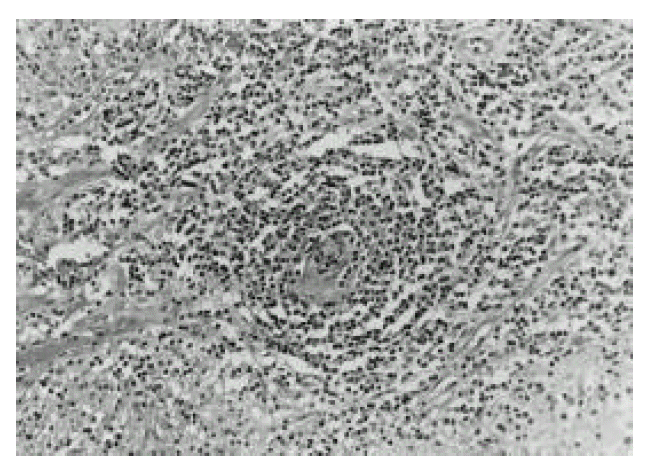

Figure 2.

Marked perivascular lymphocytic infiltration noted, and some in the wall of this arteriole as well (H&E stain, original magnification × 100).